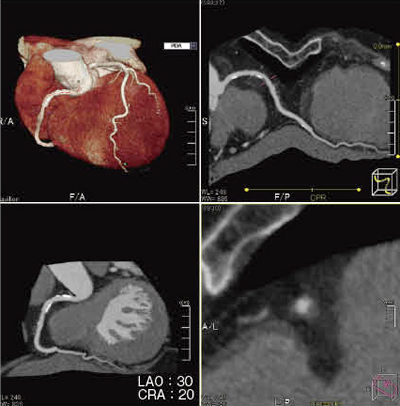

特筆すべき点は,冠動脈や血管動脈壁の抽出能が飛躍的に向上したことと,これまで一般的に使用されているVR画像やMIP画像,CPR画像,Cross Cut画像に加え,CathView(図2)という新たな画像表示方法を追加していることである。CathViewは,血管造影装置で得られる画像のangulationと比較を可能とした画像表示法である。さらに,血管内腔のみならず,血管壁や周辺臓器の情報も同時に投影することができるというCPR画像の利点も持ち合わせている。 |

図2 Plaque Viewing softwareにおける解析画像 |